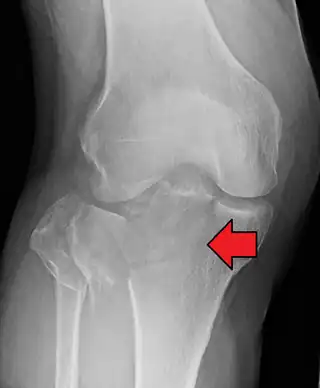

Fractura de meseta tibial leve en vista con Rayos X AP en la rodilla

Una fractura de meseta tibial vista con rayos-X